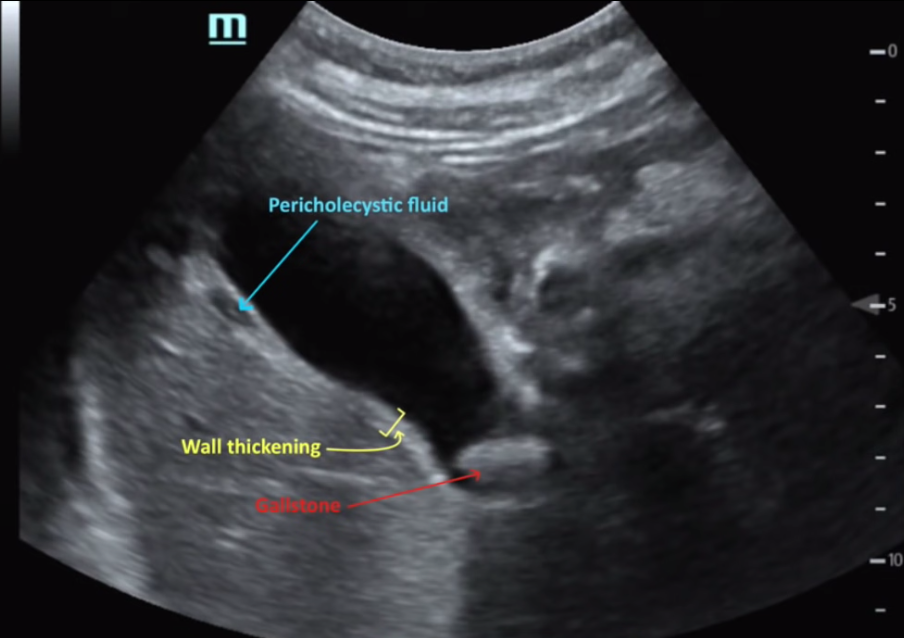

Name first step: Cholecystitis

RUQ ultrasound (2/3 criteria)

Describe tx: Cholecystitis

Cholecystectomy within 72h